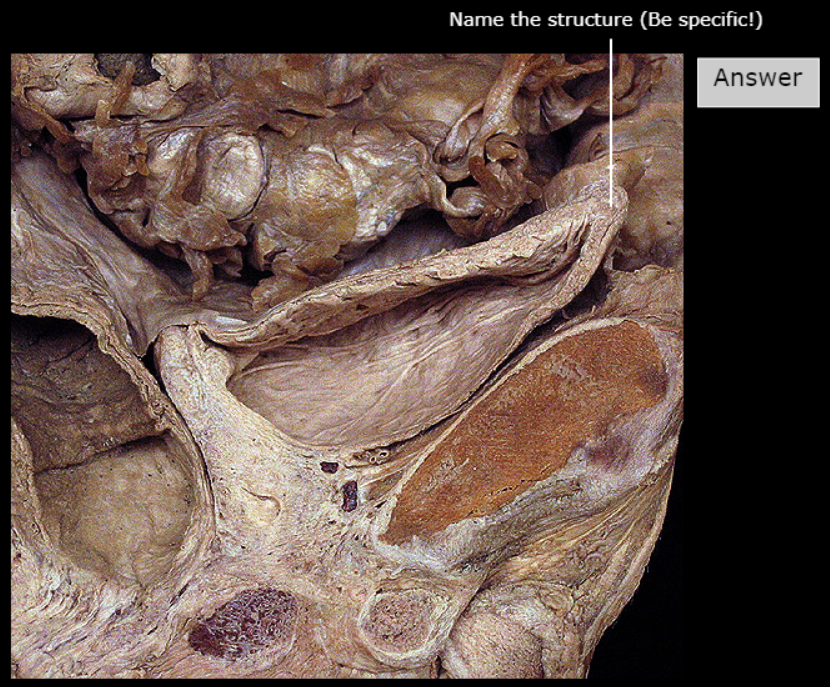

Fundus of Uterus